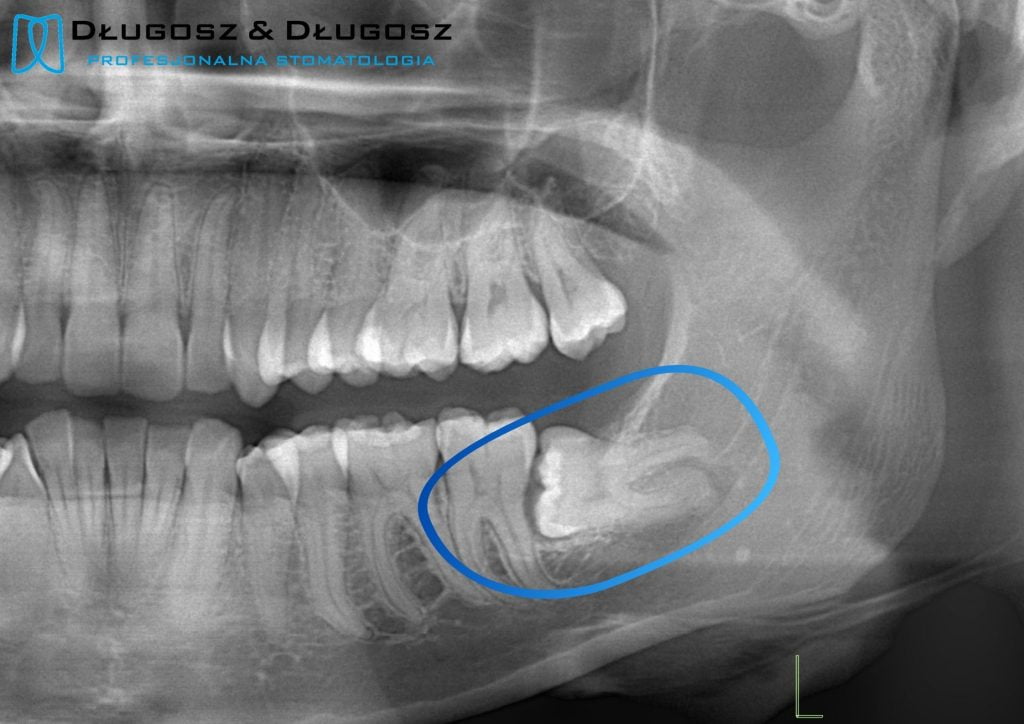

Дентальная галерея: ретинированный зуб клык и его лечение

Раздел: Компас решений